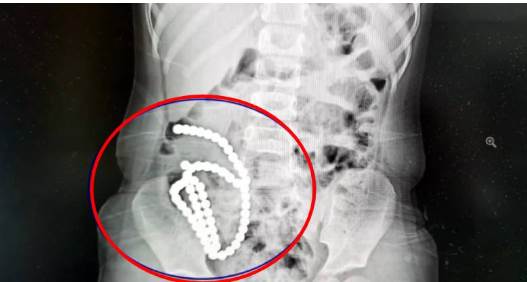

經過將近2小時的手術,醫師將多達61顆磁力珠從女童的腸胃裡取出。

副院長兼腔鏡中心主任高志剛醫師表示,女童並非一下子把磁力珠通通吞下肚,而是分次慢慢誤食。前後吞下去的珠子因為磁力相吸,「2顆巴克球之間就會有腸管壁夾在中間,慢慢腸子就穿孔了」。高醫師說明把磁力珠取出後,女童的腸壁破了14個洞,雖然手術成功修補,但仍對健康造成極大的損害,「一輩子腸沾黏、腸梗阻的風險都很大」。